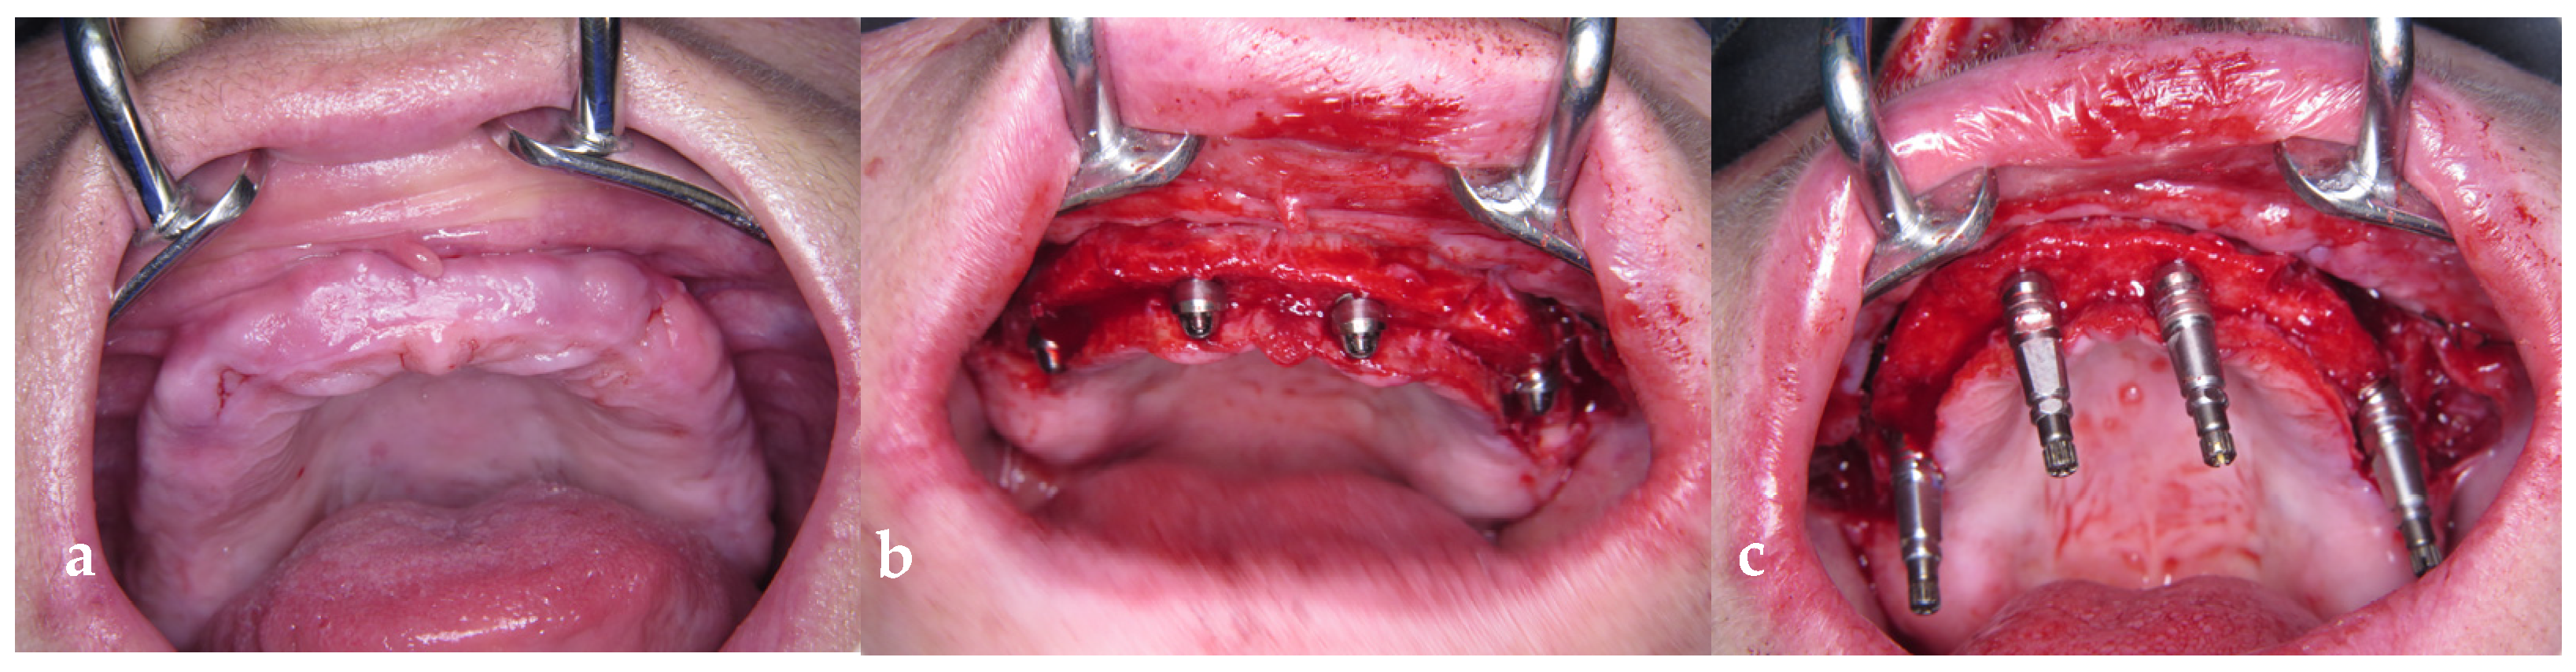

2.3. Surgery

2.4. Provisional Prosthetic Procedure